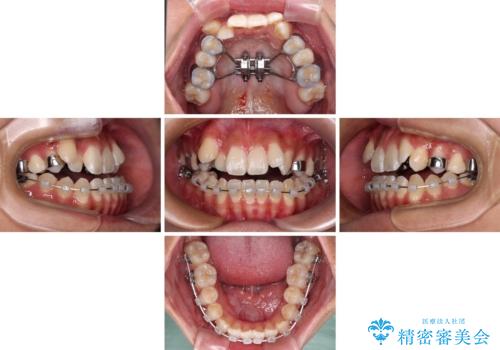

上顎歯列が狭窄していたため、急速拡大装置により上顎骨を側方に拡大し、その後ワイヤー装置にて矯正治療を行うこととしました。

急速拡大装置で上顎骨を十分に拡大できたことで、非抜歯で八重歯を歯列に納めることができました。